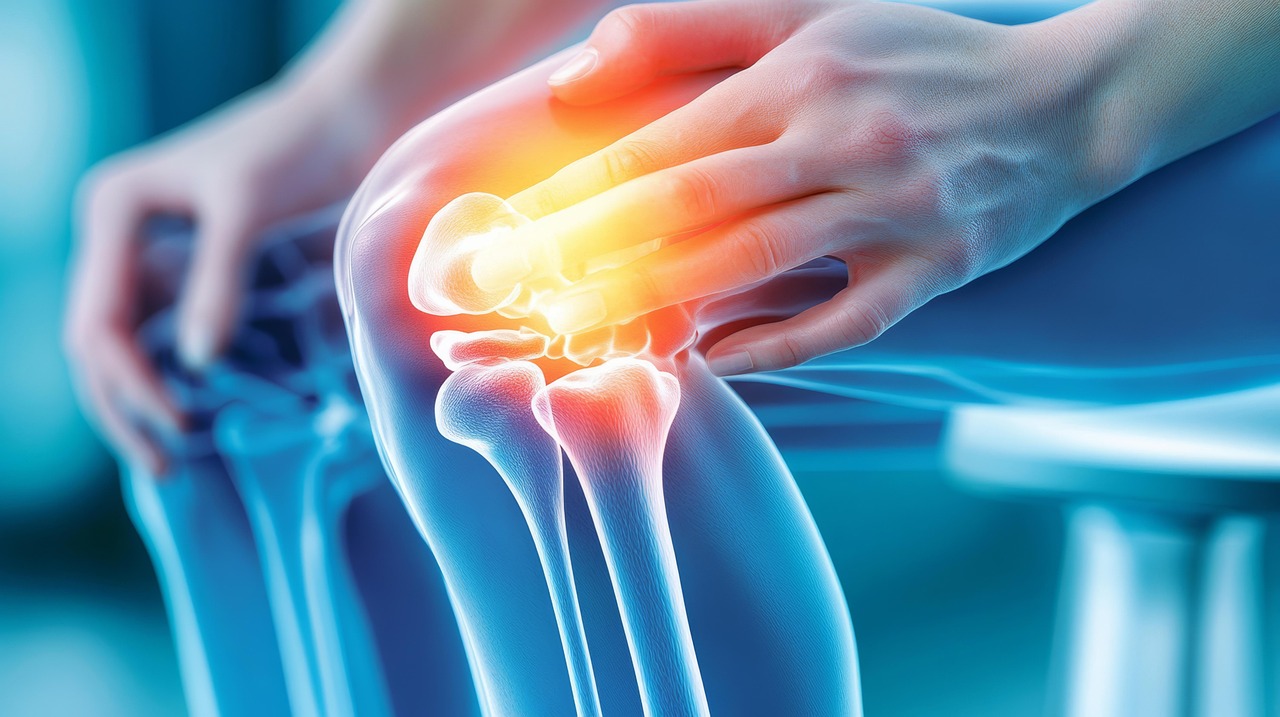

부위와 상황별 증상 구분법

계단에서 아픈가요? 아니면 앉았다 일어설 때 아픈가요?

- 계단 오를 때 무릎 안쪽 통증 → 반월상연골 손상 의심

- 앉았다 일어날 때 무릎 앞쪽 통증 → 슬개골 연골 연화증 가능성

- 계단 내려올 때 통증이 심해진다 → 퇴행성 관절염 가능성 ↑

통증 위치로 보는 원인 구분

- 무릎 안쪽 통증 → 관절염, 반월상연골 손상

- 무릎 바깥쪽 통증 → 장경인대염 등 외측 인대 문제

- 무릎 앞쪽 통증 → 슬개골 연골 연화증, 슬개건염

- 무릎 뒤쪽 통증 → 오금 낭종(베이커 낭종), 반월상연골 뒤쪽 손상